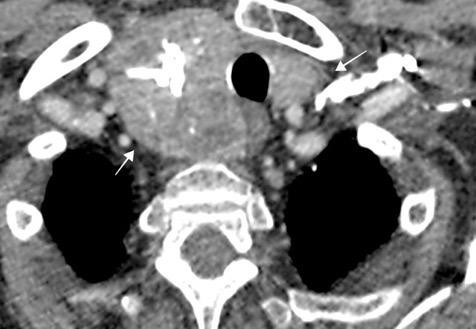

Triada de Garland

Ganglios paratraqueales derechos e hiliares bilaterales

95% de pacientes tienen ganglios hiliares bilaterales aislados o con afectación mediastínica (espec. paratraqueal derecho).

Criado E et al. Pulmonary sarcoidosis: typical and atypical manifestations at high-resolution CT with pathologic correlation. Radiographics. 2010